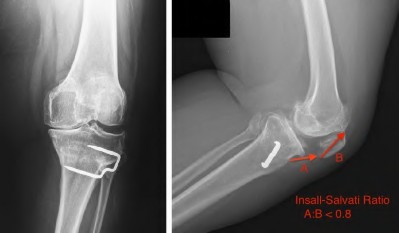

Elevation of the joint line during TKA (often resulting from excessive distal femoral resection and using a thicker polyethylene insert) most commonly leads to which of the following complications?

Explanation